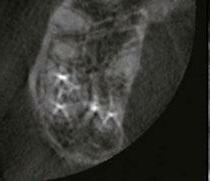

Figure 1: This CT reconstruction of the apical third of a premolar root shows the challenge we often encounter when negotiating root canals to their terminal lengths. In just these two canals, there are five potential impediments to passage of the first negotiating file to length

The other technological advances in rotary file manufacturing have been achieved through improved flute angles, file tip geometry, and cross-sectional core strength (Figure 2). Typical tapered-file flute geometry has flute angles that are tighter at the shank end and more open near the file tip, which contributes to files threading into canals when their shank end flutes approach the orifice level. When that happens, file tips are propelled into the canal; and if they have lesser flute angles, they are more likely to hang an edge, a major cause of file separation. Files with consistent flute angles have greater tip flexibility and strength, while their shank end flutes resist threading and cut more effectively. This flute-angle geometry is imperative when using rotary instruments as FFL (Buchanan, 2019). Without it, breakage too easily occurs, even when using a light touch and a low-torque limit. Adequate core strength is also critical in these narrowest of files; miniKUT Rotary Files have different cross-sectional geometries, depending on their purpose — just two flutes for the larger shaping files to aid cutting function, and four flutes for the smaller EZP rotary negotiating files to add torsional strength (Oh, et al., 2010).

With these engineered solutions that minimize breakage, the only remaining concern about using rotary negotiation as FFL is the possibility of rotary file tips blocking, ledging, or perforating the often tortuous apical regions of canals. This is why file tips on these rotary negotiators are fully radiused. This extremely passive tip geometry not only prevents ledging and perforation, but also actually causes these rotary files to kind of “bump” around impediments that would absolutely be engaged by an unbent hand file. While blockage is always a concern when advancing a file into apical regions of vital canals during negotiation procedures, it turns out that the way hand files function when used in a watch-wind, push-pull manner is actually the cause of most apical blockage.

During the development of rotary negotiation files, the overriding concern was preventing file breakage and avoiding apical blockage, ledging, and perforation (Plotino, et al., 2020). Surprisingly, the outcome was not a technique just as safe as hand-driven K-files. The outcome was a technique that is faster, easier, better, and safer than hand file manipulation.

Figure 2: PlanB’s 15-.03 miniKUT EZP Rotary Negotiation File. Note the square cross section and the aggressive rake angles of the four flutes, providing torsional strength with cutting efficiency (middle). The completely passive “duckbill” file tip geometry eliminates the chance of ledging curved canals during rotary negotiation as FFL (right). The side view shows flute angles that are consistent from tip to shank, preventing file threading and tip breakage (left)

The simple fact is that rotary negotiation as FFL is superior to hand file negotiation (Figures 3,4 and 6).